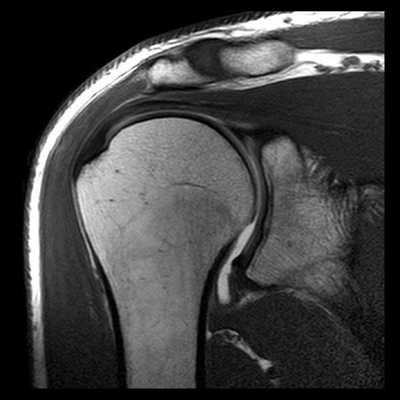

(Слева) Фронтальная косая МРТ Т2ВИ FS: пациент с I типом акромиально-ключичного вывиха после падения на область плечевого сустава. Отмечается отек вокруг акромиально-ключичного сустава без расширения сустава.

(Справа) На сагиттальной косой МРТ Т2ВИ FS у этого же пациента тоже виден отек вокруг акромиально-ключичного сустава и частичный разрыв суставной капсулы. Такие данные у пациента с болью и напряжением вокруг акромиально-ключичного сустава после травмы без расширения сустава соответствуют I типу акромиально-ключичного вывиха.

4. МРТ при травме акромиально-ключичного сустава:

• Т1 ВИ:

о Расширенный акромиально-ключичный сустав или приподнятый дистальный конец ключицы

о Разрыв акромиально-ключичной и клювовидно-ключичной связки

• Т2 ВИ FS:

о Отек мягких тканей вокруг акромиально-ключичного сустава

о Суставной выпот

о Отек костного мозга, прилежащего к суставу